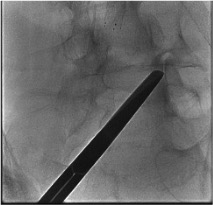

Skin entry + needle advance

Confirm position AP + lateral

Contrast arthrogram

AP fluoroscopy — needle to target

Lateral view depth confirmation

Contrast check